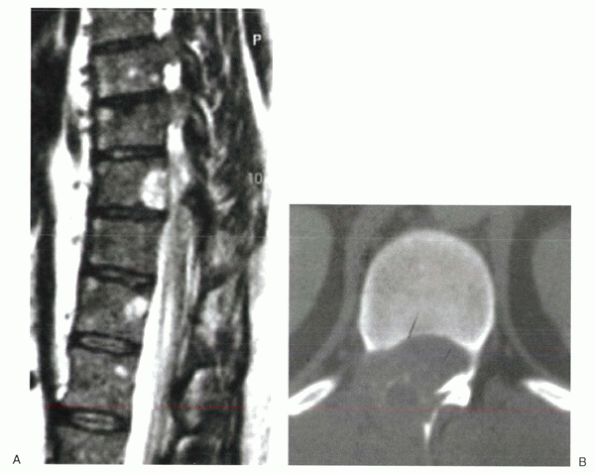

the onset of symptoms. MRI has replaced scintigraphy and CT as the

definitive modality for the detection and evaluation of suspected

spinal infection (Fig. 2-11).

![]() |

|

Figure 2-11 T1-weighted (A), T2-weighted (B), and gadolinium-enhanced (C) images of a patient with lumbar osteomyelitis.

typically do not involve the disc space and remain confined to the

vertebral body or posterior arch (Fig. 2-14).

Figure 2-14 Benign primary bone tumors most often occur within the posterior vertebral body and posterior arch. (A) Sagittal MRI shows a benign hemangioma of the posterior vertebral body that extended into the pedicle (image not shown). (B) Axial CT scan of an aneurysmal bone cyst. The patient presented with pain and myelopathy.